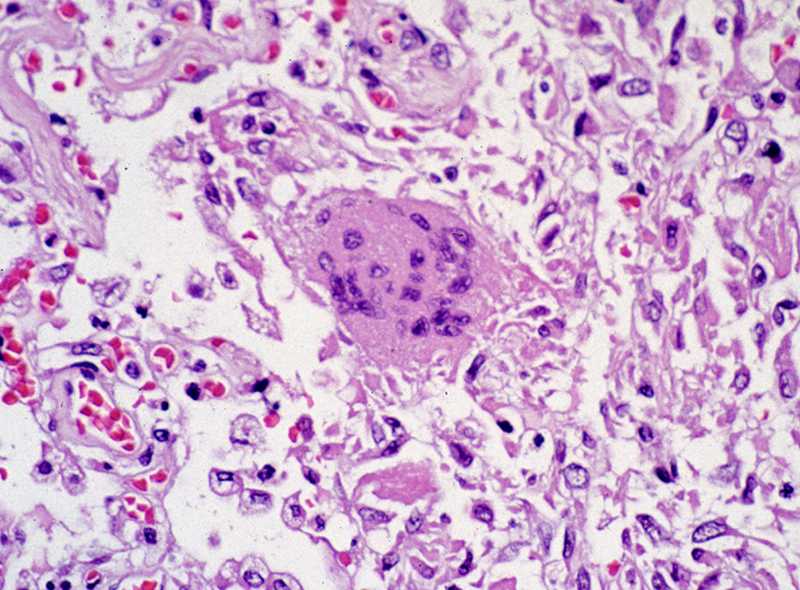

What Are Coronaviruses?

Coronaviruses are named for the crown-like spikes on their surface. They are common viruses that most people get in their lifetime. These viruses usually cause mild to moderate upper-respiratory tract illnesses.